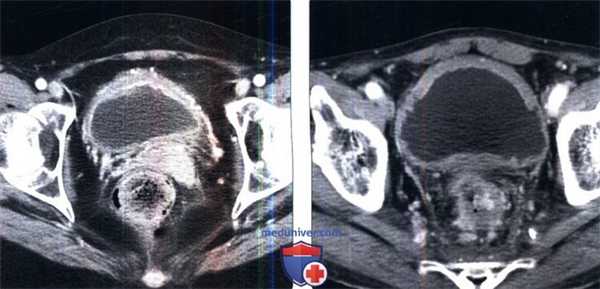

(Справа) КТ с контрастированием, аксиальный срез: эксцентричное утолщение стенки мочевого пузыря с окопопузырными воспалительными изменениями, сравнимые с циститом, вероятно вследствие хронического раздражения постоянным катетером. Гиперемия стенки свидетельствует больше в пользу цистита, чем новообразования. (Слева) КТ, аксиальный срез: выраженное утолщение стенки мочевого пузыря и наполненные кровью околопузырные кровеносные сосуды. Пациент получал терапию циклофосфамидом, который экскретируется с мочой, и эти изменения привели к воз никновению химического цистита. больные раком находятся в группе повышенного риска возникновения инфекционного цистита: анализ мочи очень эффективен при дифференцировании этих двух заболеваний.

(Справа) КТ, аксиальный срез у пациента с анамнезом недавнего внешнего радиационного облучения по поводу рака прямой кишки, определяется утолщение стенки мочевого пузыря, представляющее собой острый радиационно-индуцированный цистит.

(Слева) КТ, аксиальный срез: выраженное утолщение стенки мочевого пузыря и наполненные кровью околопузырные кровеносные сосуды. Пациент получал терапию циклофосфамидом, который экскретируется с мочой, и эти изменения привели к воз никновению химического цистита. больные раком находятся в группе повышенного риска возникновения инфекционного цистита: анализ мочи очень эффективен при дифференцировании этих двух заболеваний.